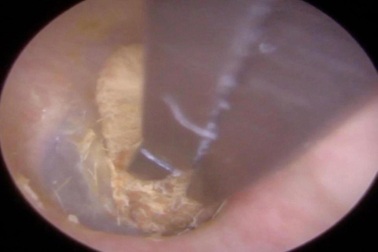

Có cục bông mắc kẹt trong tai từ 2 năm trước mà không hề hay biếtNgười đàn ông đến phòng khám ở Leicestershire đã phàn nàn về những cơn đau kéo dài và khả năng nghe hạn chế của tai phải.

00:42Video gắp cục bông kẹt 2 năm trong tai bệnh nhân ra ngoàiVideo gắp cục bông kẹt 2 năm trong tai bệnh nhân ra ngoài

Kinh khiếp cảnh quay gắp tăm bông bị kẹt trong taiBác sĩ Neel Raithatha (Anh) công bố clip nội soi gắp một miếng tăm bông lớn bị kẹt trong tai bệnh nhân tới vài ngày.